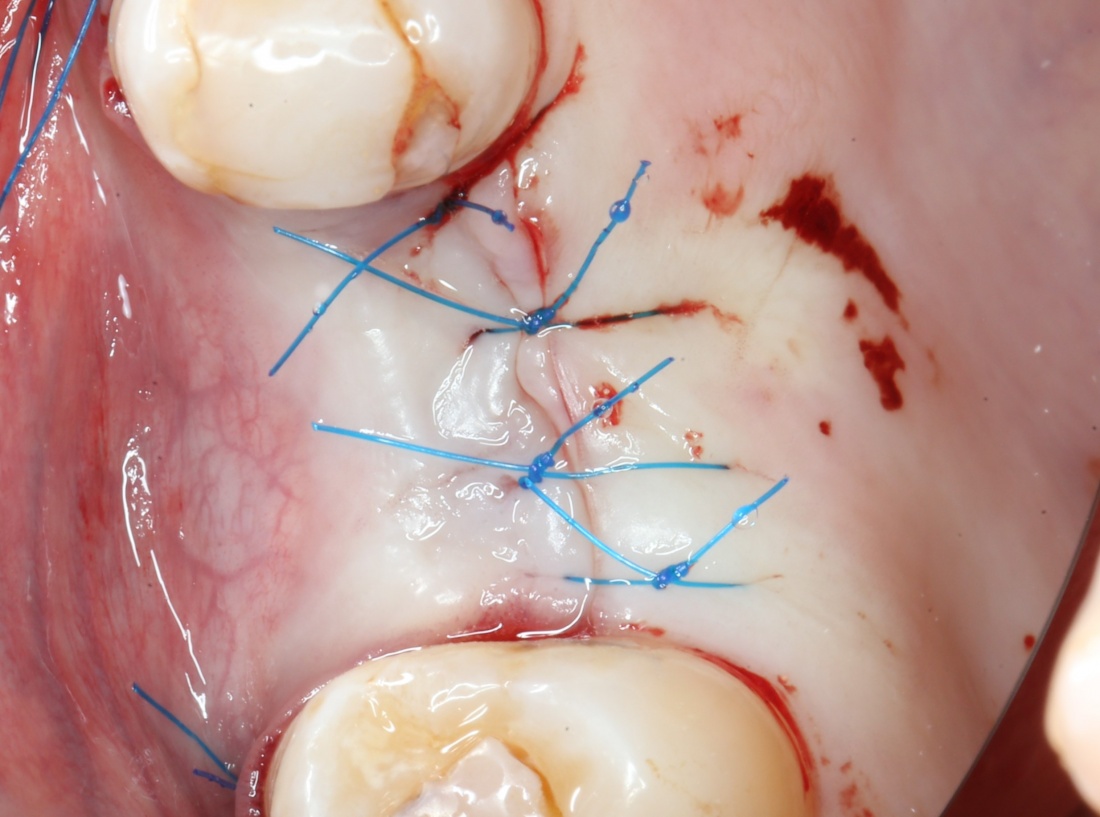

Приступаем к установке имплантата.

Если лунка подготовлена правильно, то имплантат проваливается в неё почти полностью:

Теперь заглушка. Упаковка заглушки еще более неудобная, чем упаковка имплантата:

Рекомендации после операции можно посмотреть здесь>>

Первый этап имплантологического лечения завершён.